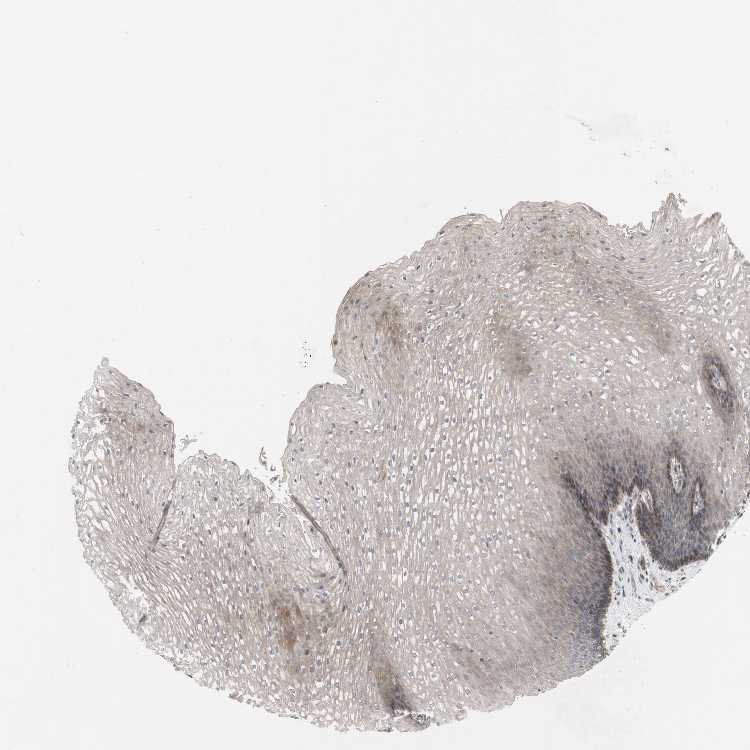

ESOPHAGUS - Antibody stainingi

Antibody staining in the annotated cell types in the current human tissue is reported as not detected, low, medium, or high, based on conventional immunohistochemistry profiling in selected tissues. This score is based on the combination of the staining intensity and fraction of stained cells.

Each image is clickable and will lead to virtual microscopy that enables deeper exploration of all samples and also displays staining intensity scores, fraction scores and subcellular localization as well as patient and tissue information for each sample.

Antibody HPA009291

Squamous epithelial cells Medium